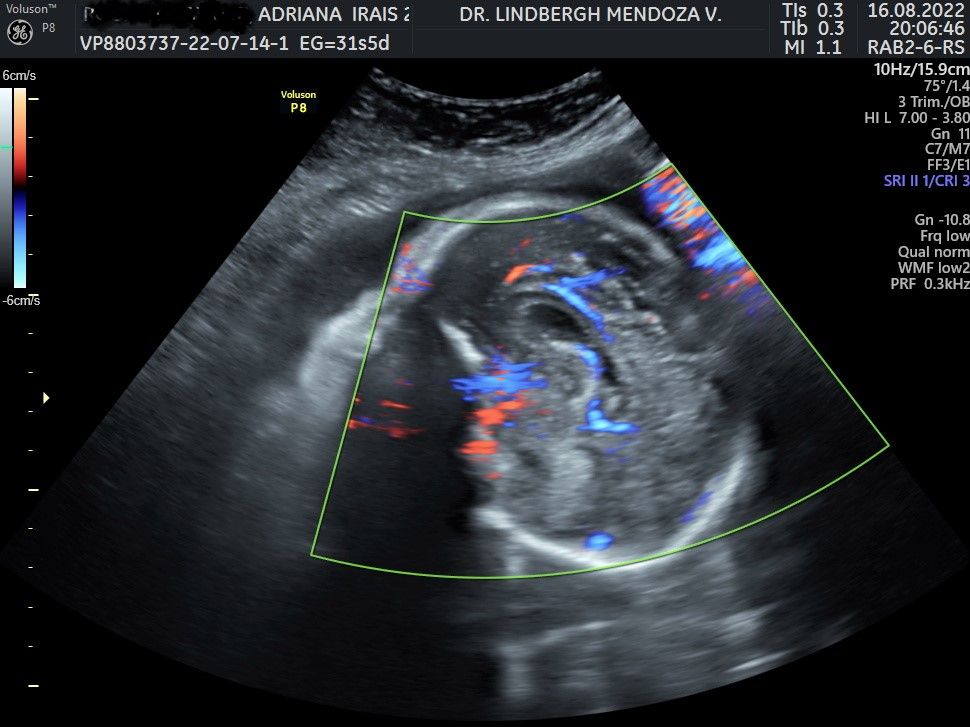

Ultrasonido de crecimiento más doppler (30-34 semanas)